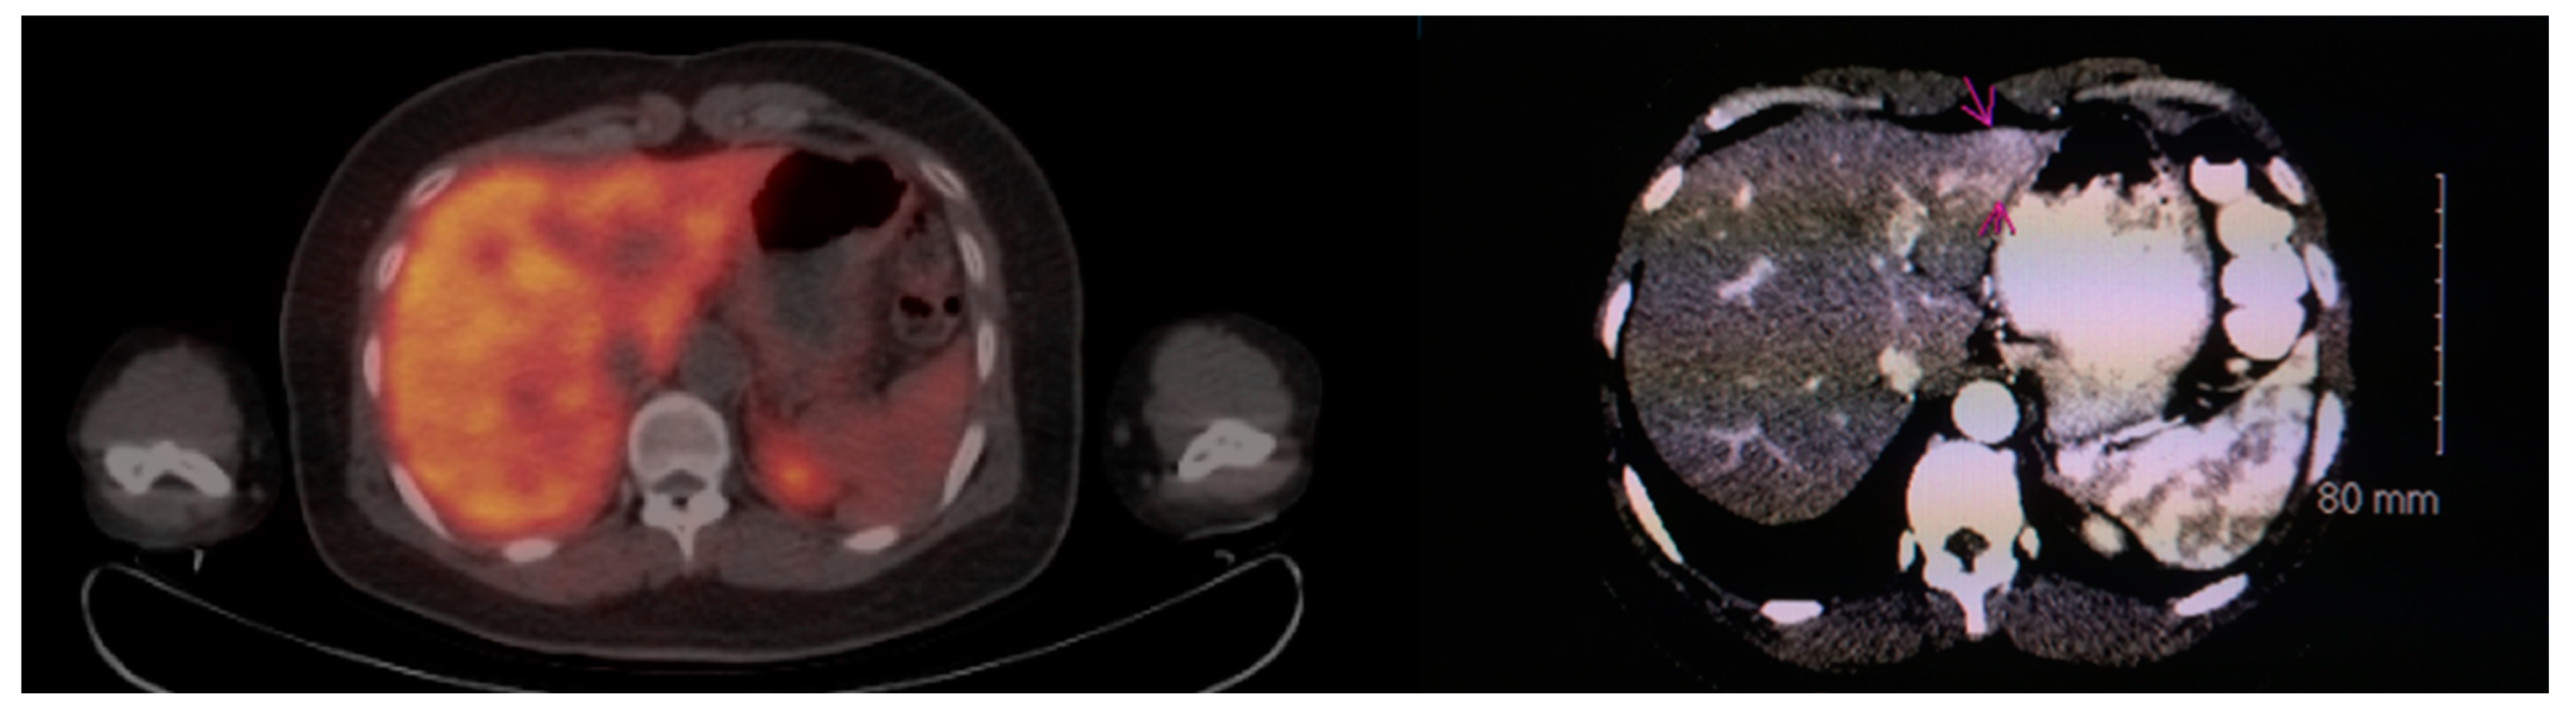

Multiple foci of increased FCh uptake in the liver consistent with multifocal or multinodular HCC (example, Figure 1) were noted in 8 of the 13 patients with increased primary tumor uptake. Of these, the areas of increased FCh uptake were adjacent to the treatment site (examples, Figure 2 and Figure 3) in 2 patients treated by local tumor ablation and 1 patient treated by liver resection. In one newly diagnosed case, PET demonstrated heterogeneous tumor FCh uptake with increased peripheral uptake and markedly diminished central uptake (Figure 4). Pathology in this case revealed a highly-necrotic tumor with Edmondson-Steiner grade 3 differentiation.

Figure 4.

Metabolic heterogeneity in HCC. Corresponding PET/CT (left) and PET (right) shows a heterogeneous region of increased uptake within the liver in this patient with newly diagnosed liver mass. Two small satellite tumors (arrows) are adjacent to the dominant mass (arrowheads surround). Histologically, this was a poorly differentiated HCC tumor.